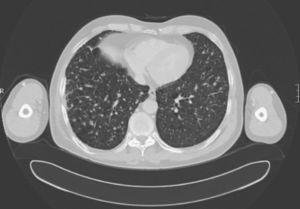

After discussion with the oncological department six months after surgery, palliative chemotherapy with the antiangiogenic drug sorafenib, a tyrosine kinase inhibitor, was decided upon. The patient did not tolerate regular cycles due to the occurrence of hand-foot syndrome. Subsequent controls with chest X-rays (Fig. 3) and CT scans every six months (Fig. 4) showed no nodule changes or decreases in thyroglobulin levels. The last value found on suppressant therapy was 1,921ng/mL with negative antithyroglobulin antibodies.

Figure 4.

CT scan of the chest.